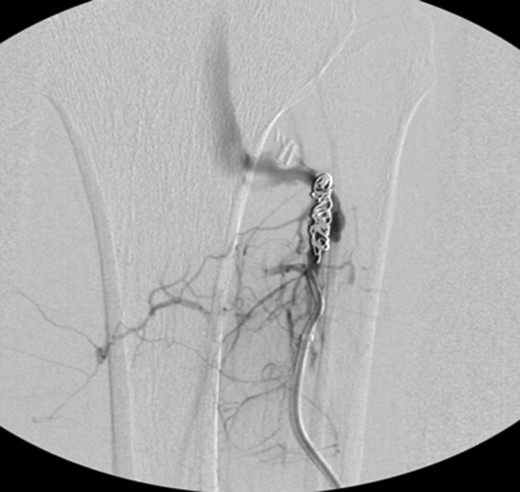

Patient underwent a left lower extremity angiogram. During the procedure she was found to have patent aorta and bilateral common iliac artery. There was no disease visualized in the left external iliac artery, common femoral artery (CFA), SFA, patent previously placed stent, patent above and below the knee PA and two vessel run off to the foot (Fig. 1). Upon delayed fluoroscopic images we identified contrast filling the deep venous system rather quickly suggesting a high volume fistula (Fig. 2). We then identified the fistula between ATA and ATV. Although ATA was previously ligated there was retrograde filling of the artery from unnamed branches, which communicated with the venous system as shown in. In the midcalf (ATA) was cannulated with a micropuncture needle. Micropuncture wire was inserted and a 5-Fr sheath was inserted after exchanging over wire. At this point VortX coils (Boston Scientific) were placed from the curve of ATA until the whole AVF was sealed. Anterograde angiogram showed no flow through the fistula (Figs 3 and 4). There was a palpable PT and DP pulse at the completion of the procedure. Sheath was removed, pressure dressing applied. Patient was discharged home same day. Recovery has been unremarkable. Three months follow-up claudication symptoms have significantly improved.

Fluoroscopy showing; left external iliac artery (EIA), common femoral artery (CFA), superficial femoral artery (SFA), patent previously placed stent, patent above and below the knee popliteal artery (PA) and two vessel run off to the foot.